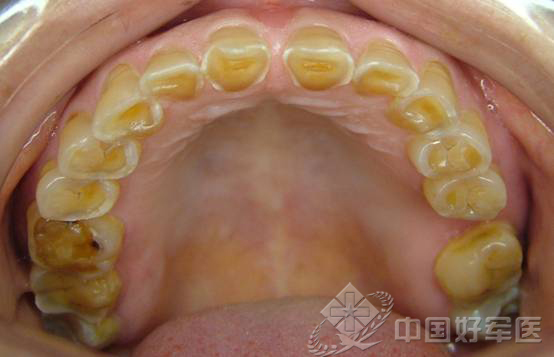

2.磨牙癥是牙在無(wú)意識(shí)狀態(tài)下承受一定強(qiáng)度咬合力的同時(shí),下頜作一定節(jié)律的運(yùn)動(dòng)或表現(xiàn)出較大運(yùn)動(dòng)傾向的現(xiàn)象。常見(jiàn)有日磨牙、夜磨牙和緊咬牙三種表現(xiàn)形式。磨牙癥是一種常見(jiàn)的功能性疾病,久患此癥,不僅影響自己和他人休息,而且可以引起肌肉疲勞、疼痛、牙齒重度磨損以及顳頜關(guān)節(jié)紊亂病等,應(yīng)予以重視。